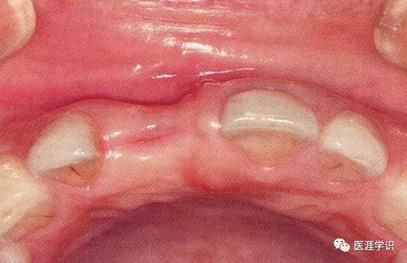

圖3-1,2 上頜中切牙存在牙體斷裂,為了能夠盡量保留牙槽骨而進(jìn)行拔牙。使用拔牙挺會容易破壞牙槽突起,所以盡可能使用車針將進(jìn)行分割拔除。